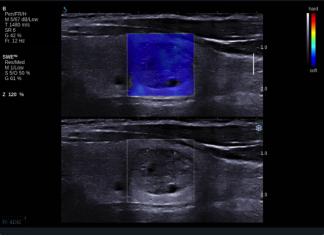

E成像(SWE)實時剪切波彈性成像技術(shù)

“聲藍”獨有的E成像(SWE)實時剪切波彈性成像技術(shù)可以廣泛應(yīng)用在實性臟器腫瘤的早期檢出和鑒別診斷、定量評估、介入穿刺引導(dǎo)、各類疾病治療前后的評價等,也是唯一全面通過美國FDA認證的實時、全幅、全定量的組織硬度可視化測量模式,因而為臨床診斷和治療,提供了安全、無創(chuàng)、有效的最新影像學全新檢查方法。目前已被應(yīng)用于甲狀腺、乳腺、肝臟、腎臟、前列腺、腸管、淋巴結(jié)、肌肉骨骼、軟組織等全身器官的鑒別診斷和定量評估。

彈性超聲與以往普超聲相比,相當于“深觸診”,可以更加直觀地“接觸到”軟組織的形態(tài),并且速度可達到1厘米/秒。與此同時,它的畫面是連續(xù)性的,具有以往單點式的超聲設(shè)備無可比擬的優(yōu)勢。它的“彈性”級別也是最高的,特別適應(yīng)于甲狀腺和乳腺的超聲診斷,并且配備了多個探頭,適用于人體不同部位的超聲需求。彈性超聲的引進與應(yīng)用,可對腫瘤的良惡性鑒別診斷及肝纖維化的無創(chuàng)診斷提供重要依據(jù),可明顯提高診斷準確率,具有非常高的敏感性、特異性,提高檢出率,為臨床診斷及治療提供重要依據(jù),盡早為患者爭取最佳的治療時機。